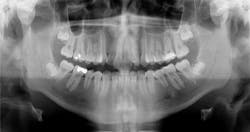

Case report A healthy 16-year-old male presents with Class II bite, an obtuse nasolabial angle, a slight, long concave profile with deficiency in the growth of the mandible, and inadequate spacing for the maxillary teeth. What are the options and talking points for this treatment plan?1. There is likely very little growth potential left in this patient, so trying to capture any remaining growth would be minimal.

2. If we were to focus only on the occlusion (minus profile, etc.), then it would be simple to extract the maxillary 4’s (1st bicuspids) and then acquire a somewhat ideal alignment of the arches.

3. In reference to point No. 2, orthodontic treatment planned without mandibular jaw advancement surgery in these types of cases generally will build in more dental compensations for skeletal variation (2), as the profile is compromised even more with a wider nasolabial angle, longer profile, and thus limiting the ability for any future facial profile correction.

4. The ideal treatment and recommendation would be to perform a lower jaw advancement surgery to give an ideal position of skeletal and dental components. Worms et al. reported that the total interrelationships of surgical and orthodontic contributions are in the best care and interest of the patient long term. (2)

It could be concluded with the aforementioned talking points that there is not a right or wrong way to proceed in cases like this. Some options are better than others, but this is the take-home point: If a Class II patient (as presented herein) does have the upper 4’s removed, it exacerbates the existing profile and limits virtually any potential for a correction of profile in the future. It is, therefore, vital to discuss all risks, benefits, complications, and alternatives so the patient can make the best decision possible. Assuming no regard to cost or possible complications, the mandibular advancement would be considered by most to be the preferential treatment in this case, as it resolves the core problem — mandibular deficiency. In this case, the patient was not willing to undergo a surgical procedure at this time, so the treating orthodontist advised the family against the removal of maxillary teeth in order to preserve facial profile and allow for possible future mandibular advancement procedure.